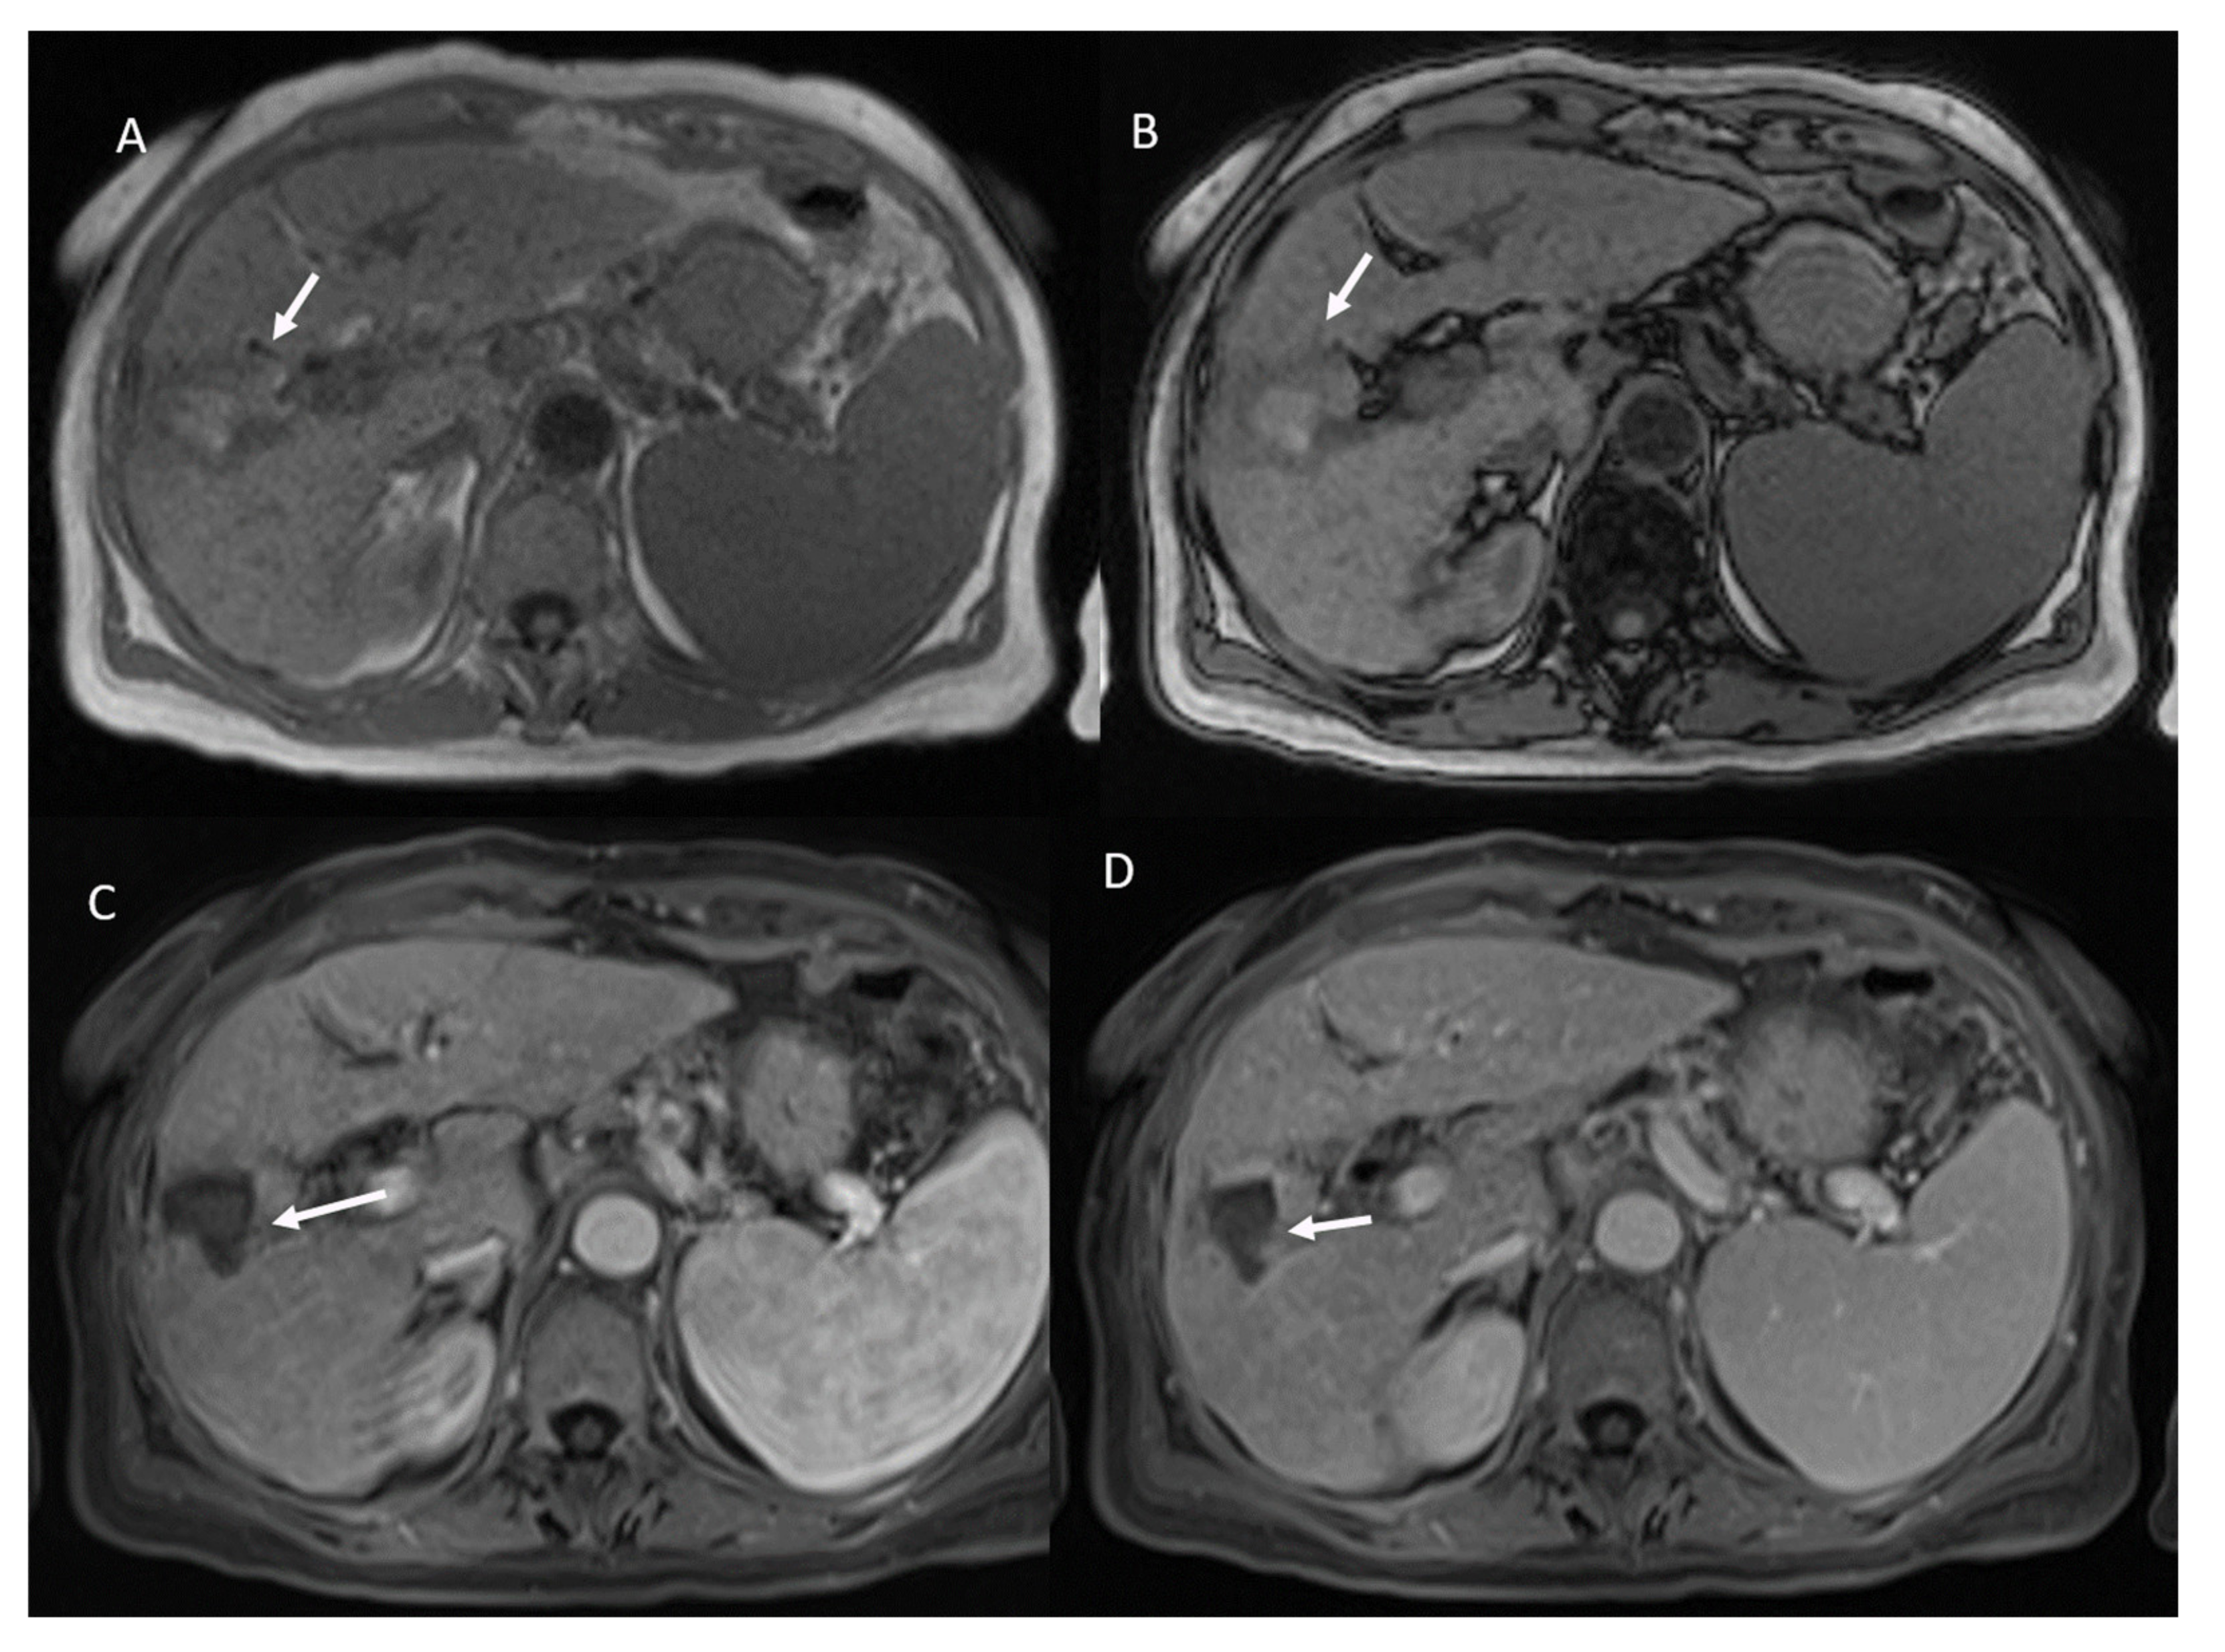

- 21 showed APHE and 2 rim APHE during arterial Phase (Figure 2).

- 23 showed wash-out appearance during portal phase and hypointense SI in equilibrium phase (Figure 2).

- 53 showed non rim APHE and 60 hypointense SI during arterial phase (Figure 5).

- 3 showed peripheral washout appearance and 110 hypointense SI in portal phase (Figure 5).

- 113 lesions were hypointense in equilibrium phase.